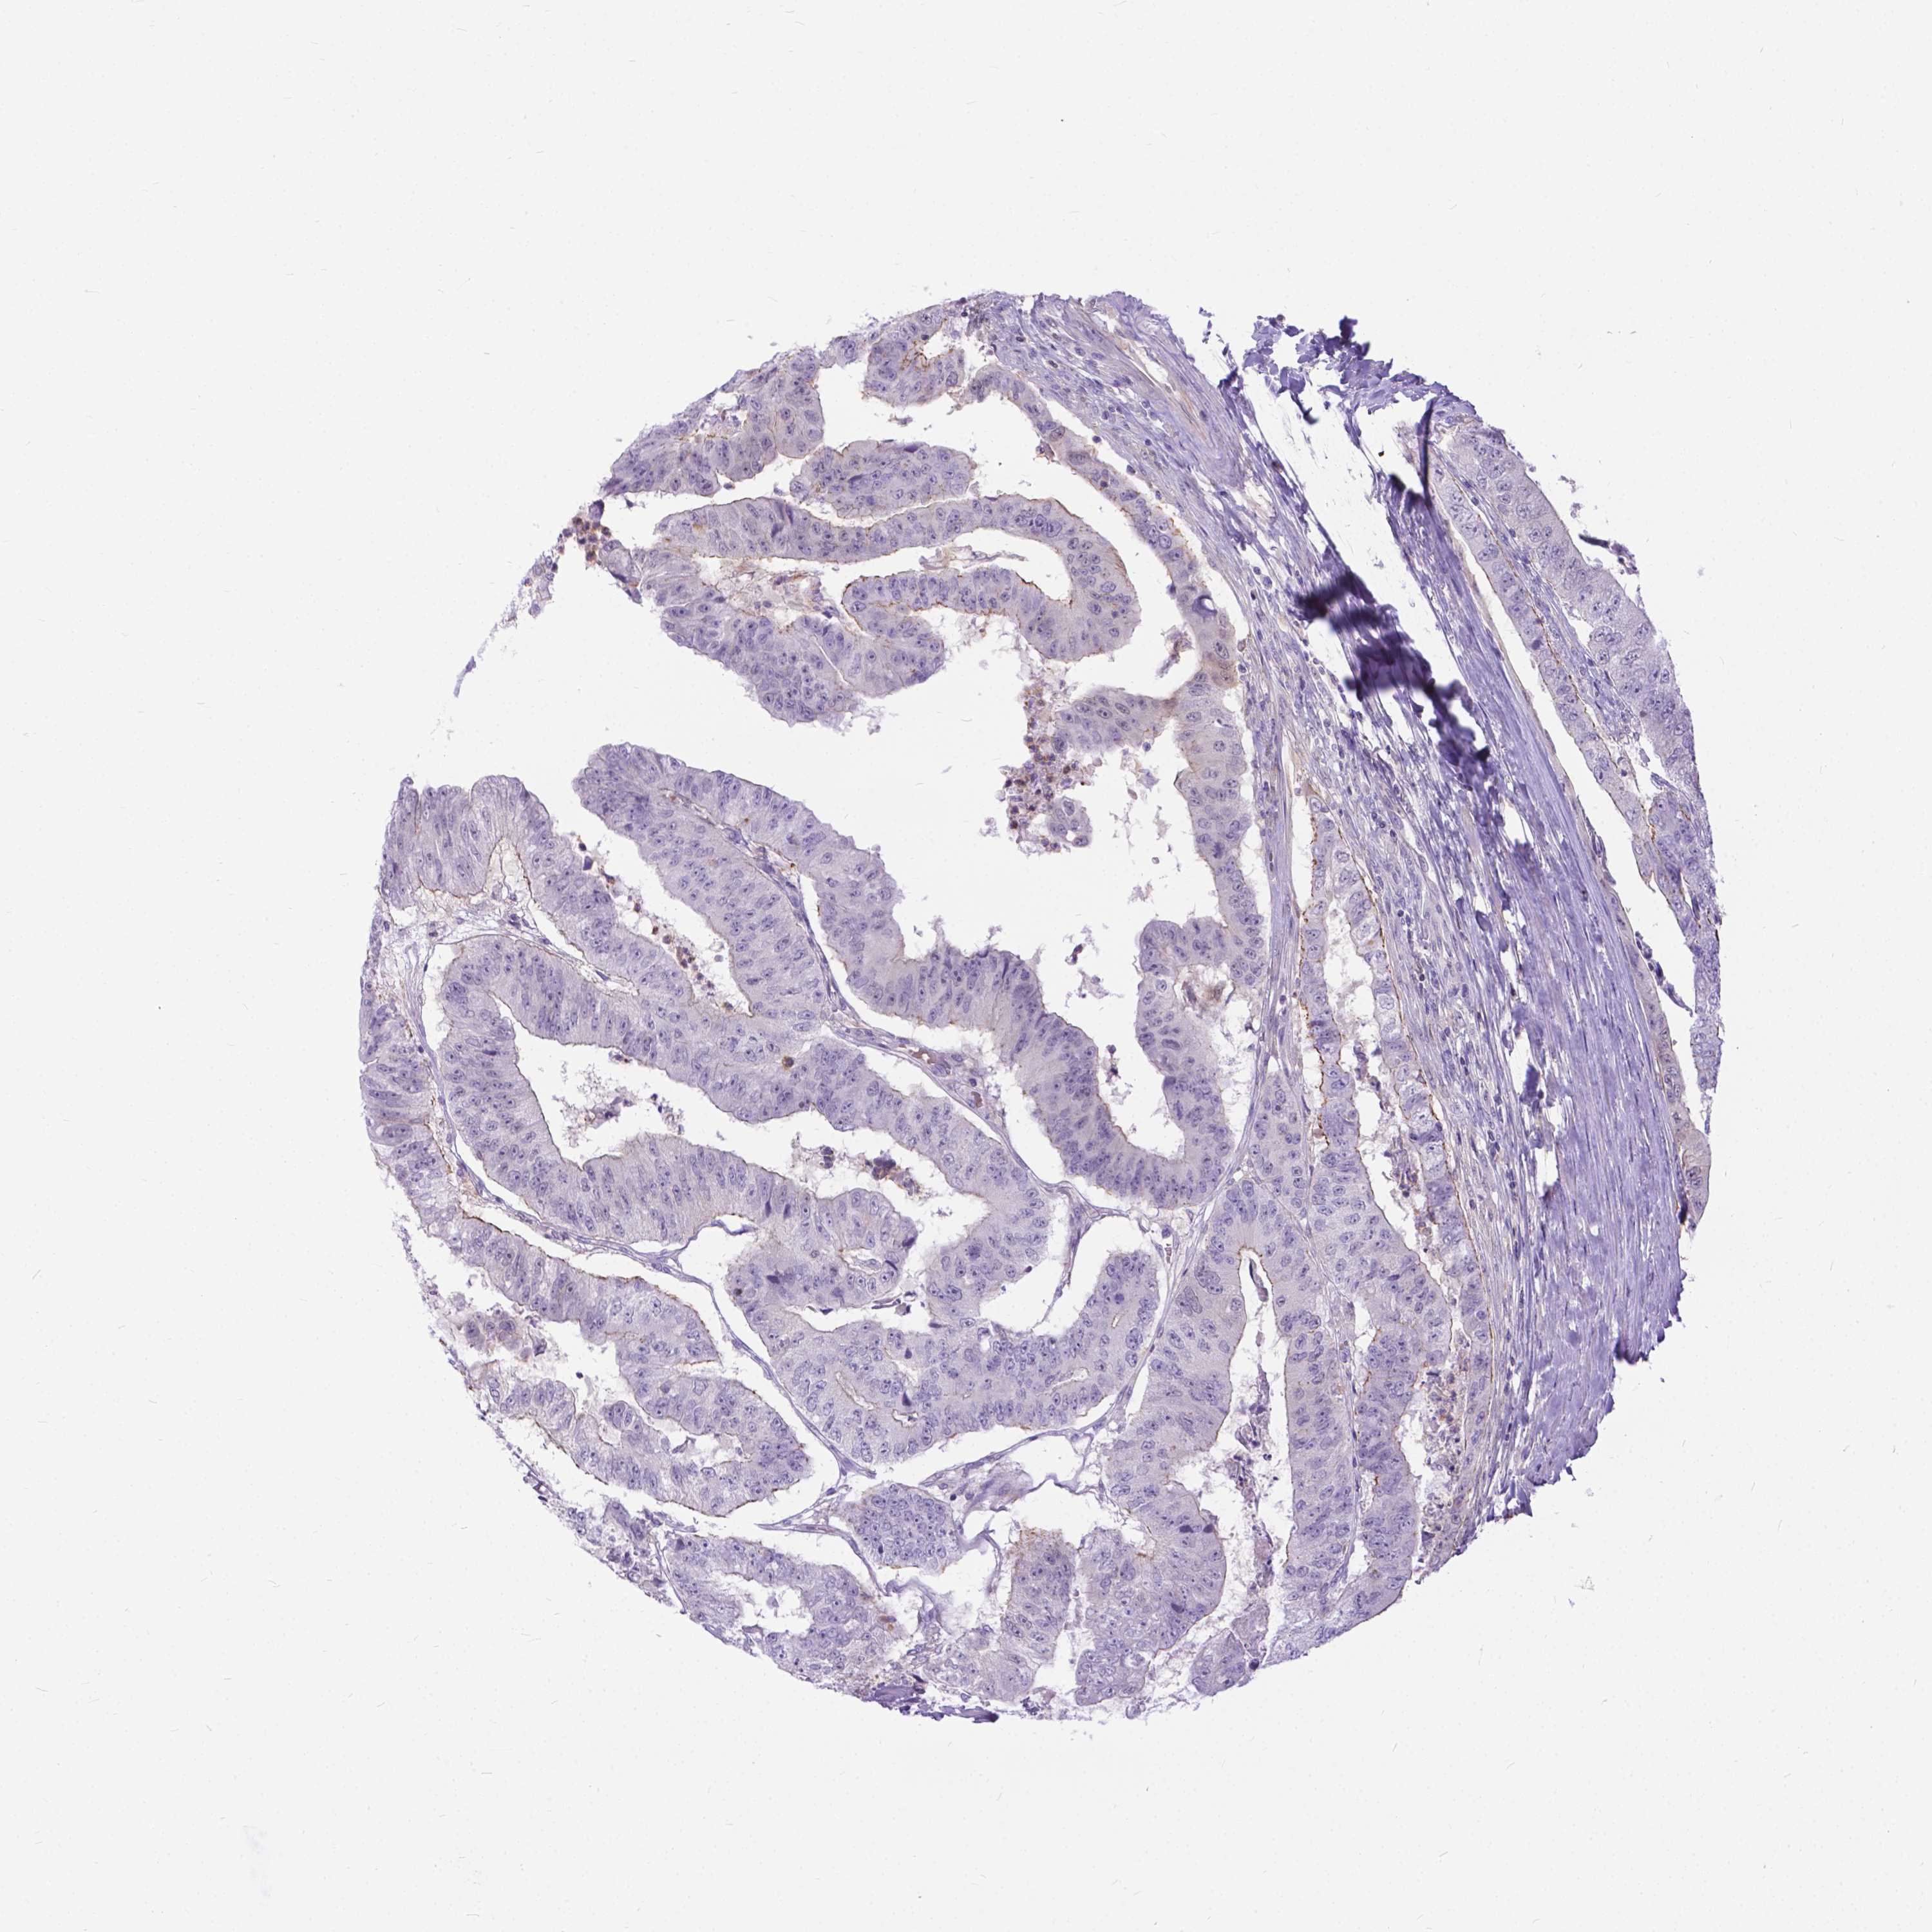

CANCER COLORECTAL CANCER Show tissue menu

Colorectal cancer

Human cancer

Colon adenocarcinoma